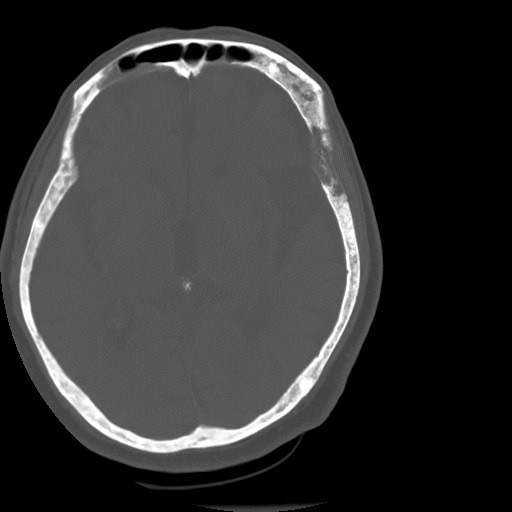

A) Schädel-CT eines 70-jährigen Patienten. B) Schädel-CT eines 30-jährigen Patienten. In einem Fall liegt eine Fibröse Dysplasie vor, in dem anderen ein Morbus Paget? Welches Bild zeigt am ehesten welche Erkrankung und warum?